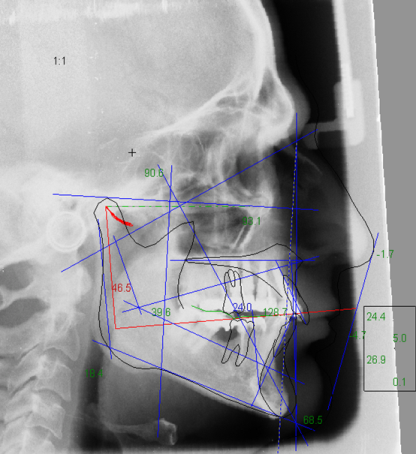

Tutti i nostri casi vengono pertanto sottoposti ad uno studio completo con una serie di esami: Esame assiografico per documentare le dinamiche articolari e contemporaneamente per rilevare le inclinazioni delle eminenze condilari.

Esame cefalometrico da effettuarsi sulla radiografia del profilo del cranio per correlare le inclinazioni delle guide incisali e canine con quelle delle eminenze articolari precedentemente rilevate dall’assiografia. Lo stesso esame ci fornirà le caratteristiche antropometriche del caso e fornirà ulteriori dati per definire un piano di cura anche in termini ortodontici.

Tutti i dati assiografici e cefalometrici sono elaborati da un software dedicato che consente di rilevare in modo dettagliato tutte le caratteristiche antropometriche e funzionali del sistema cranio mandibolare.

Esiste un’ armonia geometrica che consente od ostacola il buon funzionamento del sistema: la sintesi del nostro studio è quella di identificare ed interpretare questa geometria funzionale.